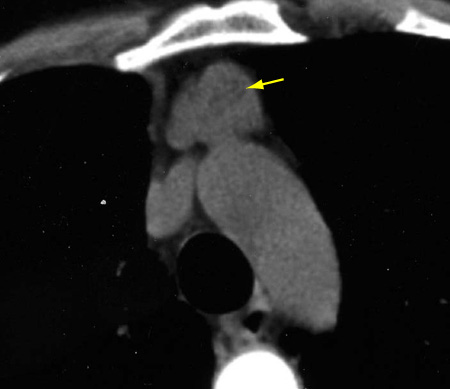

A TC de tórax geralmente mostra um aumento da forma típica do timo (bilobado) sem uma massa arredondada dominante ou distinta.[Figure caption and citation for the preceding image starts]: Tomografia computadorizada (TC) do tórax mostrando timo proeminente com aparência bilobada, consistente com hiperplasia tímicaDo acervo de Cameron Wright, MD; usado com permissão [Citation ends].